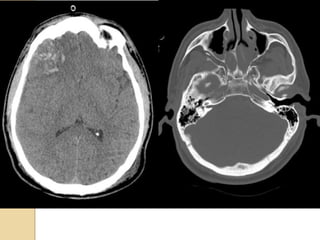

EPIDURAL HEMATOMAEPIDURAL HEMATOMA Locatedbetween the skull and periosteum Due to laceration of the middle meningeal artery or dural veins Can cross dural reflections but is limited by suture lines Lentiform shape (but concave shape in SDH)

Subarachnoid hemorrageSubarachnoid hemorrage Canoriginate from direct vessel injury, contused cortex or intraventricular hemorrhage. Look in the interpeduncular cistern and Sylvian fissure Usually focal (but diffuse from aneurysm) Can lead to communicating hydrocephalus